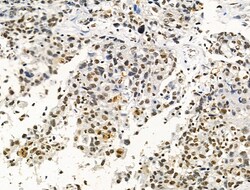

| Immunohistochemistry (Paraffin), Western Blot, Immunocytochemistry | |